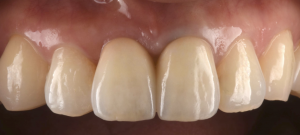

根が縦に割れてしまった前歯をインプラントで治療した症例【前歯部審美症例13】

初診時。前歯の歯茎が常に腫れていて痛いとのことでご来院されました。神経処置後の歯は破折のリスクが高くなってしまいます。レントゲン写真、CTで調べてみると被せものの下の根っこが縦に割れてしまっていること…